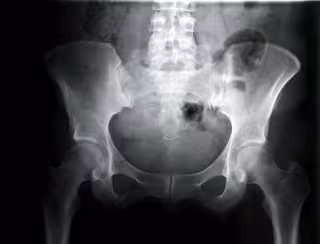

Cadera de mujer vista con rayos.

GETTY - Archivo